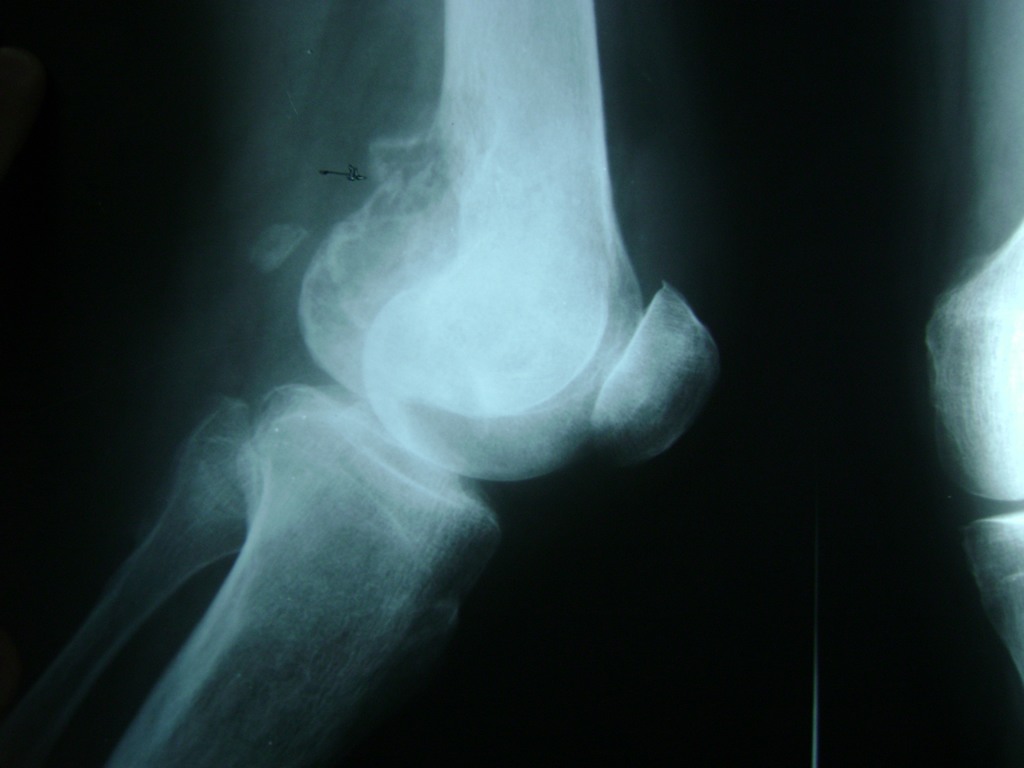

Cirugías de Peroné y Tibia

La artroscopia de rodilla es un cirugía en el cual la estructura interna de la articulación es examinada ya sea para realizar un diagnostico o para realizar un tratamiento, este procedimiento se realiza utilizando un instrumento parecido a un pequeño tubo llamado artroscopio.